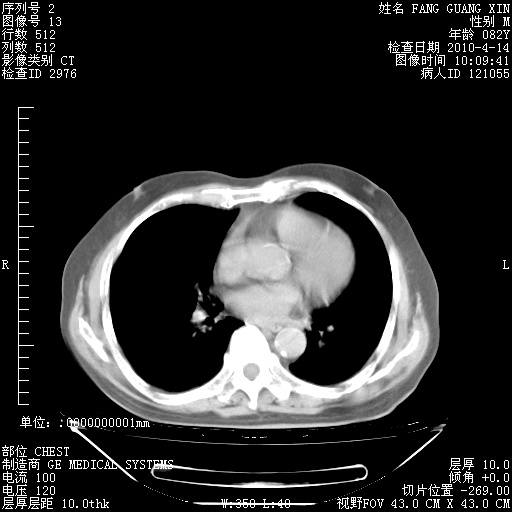

肺部CT平扫未见异常。